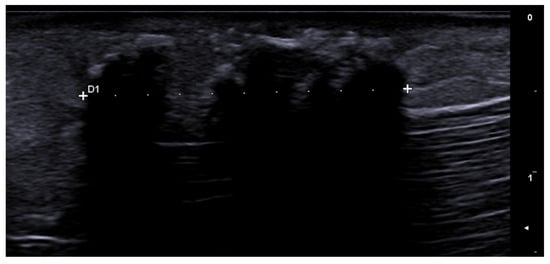

- Berritto, D.; Iacobellis, F.; Rossi, C.; Reginelli, A.; Cappabianca, S.; Grassi, R. Ultra high-frequency ultrasound: New capabilities for nail anatomy exploration. J. Dermatol. 2017, 44, 43–46. [Google Scholar] [CrossRef]